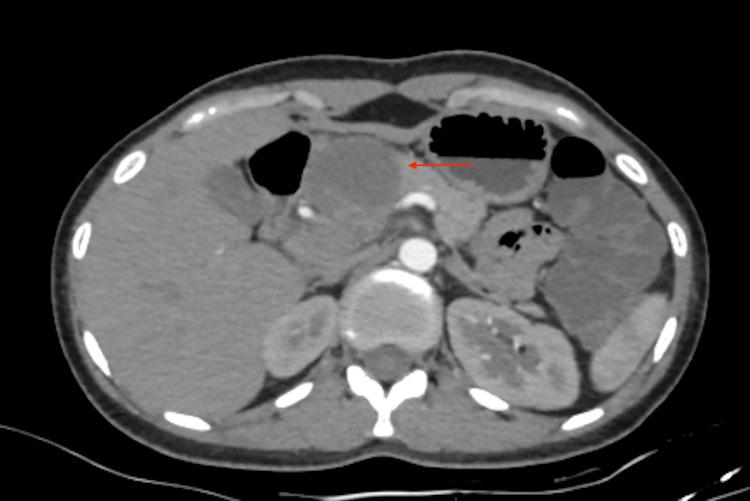

Tuberculosis (TB) continues to be a major global health burden, particularly in low- and middle-income countries, where it contributes significantly to morbidity and mortality. While pulmonary TB is the most common form, extrapulmonary manifestations, including pancreatic TB, are rare and often pose diagnostic challenges. Isolated pancreatic TB in immunocompetent individuals is exceptionally uncommon and is rarely considered in the initial differential diagnosis of a pancreatic mass. We present the case of a 26-year-old immunocompetent woman with a six-month history of persistent epigastric pain, nausea, vomiting, and progressive weight loss. Laboratory investigations revealed normocytic normochromic anemia and mildly elevated serum bilirubin levels. Contrast-enhanced computed tomography (CT) of the abdomen demonstrated pancreatic mass, leading to a provisional diagnosis of pancreatic carcinoma. However, histopathological examination of the lesion revealed features of an acute suppurative process. Further analysis of aspirated cystic fluid using the Cartridge-Based Nucleic Acid Amplification Test (CBNAAT) and Ziehl-Neelsen (ZN) staining confirmed the presence of . The patient was commenced on standard anti-tubercular therapy, which led to marked clinical improvement. On follow-up, the patient's symptoms had resolved completely, and repeat imaging demonstrated normalization of pancreatic architecture. This case highlights the importance of considering pancreatic TB as a diagnosis, even in immunocompetent individuals, particularly from endemic regions. Limitations of our study include a short follow-up period and unavailability of endoscopic ultrasound (EUS) evaluation.

结核病(TB)仍然是全球主要的健康负担,尤其是在低收入和中等收入国家,它对发病率和死亡率有重大影响。虽然肺结核是最常见的形式,但肺外表现,包括胰腺结核,很罕见,且常常带来诊断挑战。免疫功能正常个体中孤立性胰腺结核极为罕见,在胰腺肿块的初始鉴别诊断中很少被考虑。我们报告一例26岁免疫功能正常的女性病例,她有持续六个月的上腹部疼痛、恶心、呕吐和进行性体重减轻病史。实验室检查显示正细胞正色素性贫血和血清胆红素水平轻度升高。腹部增强计算机断层扫描(CT)显示胰腺肿块,初步诊断为胰腺癌。然而,病变的组织病理学检查显示为急性化脓性过程的特征。使用基于 cartridge 的核酸扩增试验(CBNAAT)和萋-尼(ZN)染色对吸出的囊液进行进一步分析,证实了……的存在。患者开始接受标准抗结核治疗,临床症状明显改善。随访时,患者症状完全缓解,重复成像显示胰腺结构正常化。该病例强调了即使在免疫功能正常的个体中,尤其是来自流行地区的个体,将胰腺结核作为一种诊断考虑的重要性。我们研究的局限性包括随访期短和无法进行内镜超声(EUS)评估。